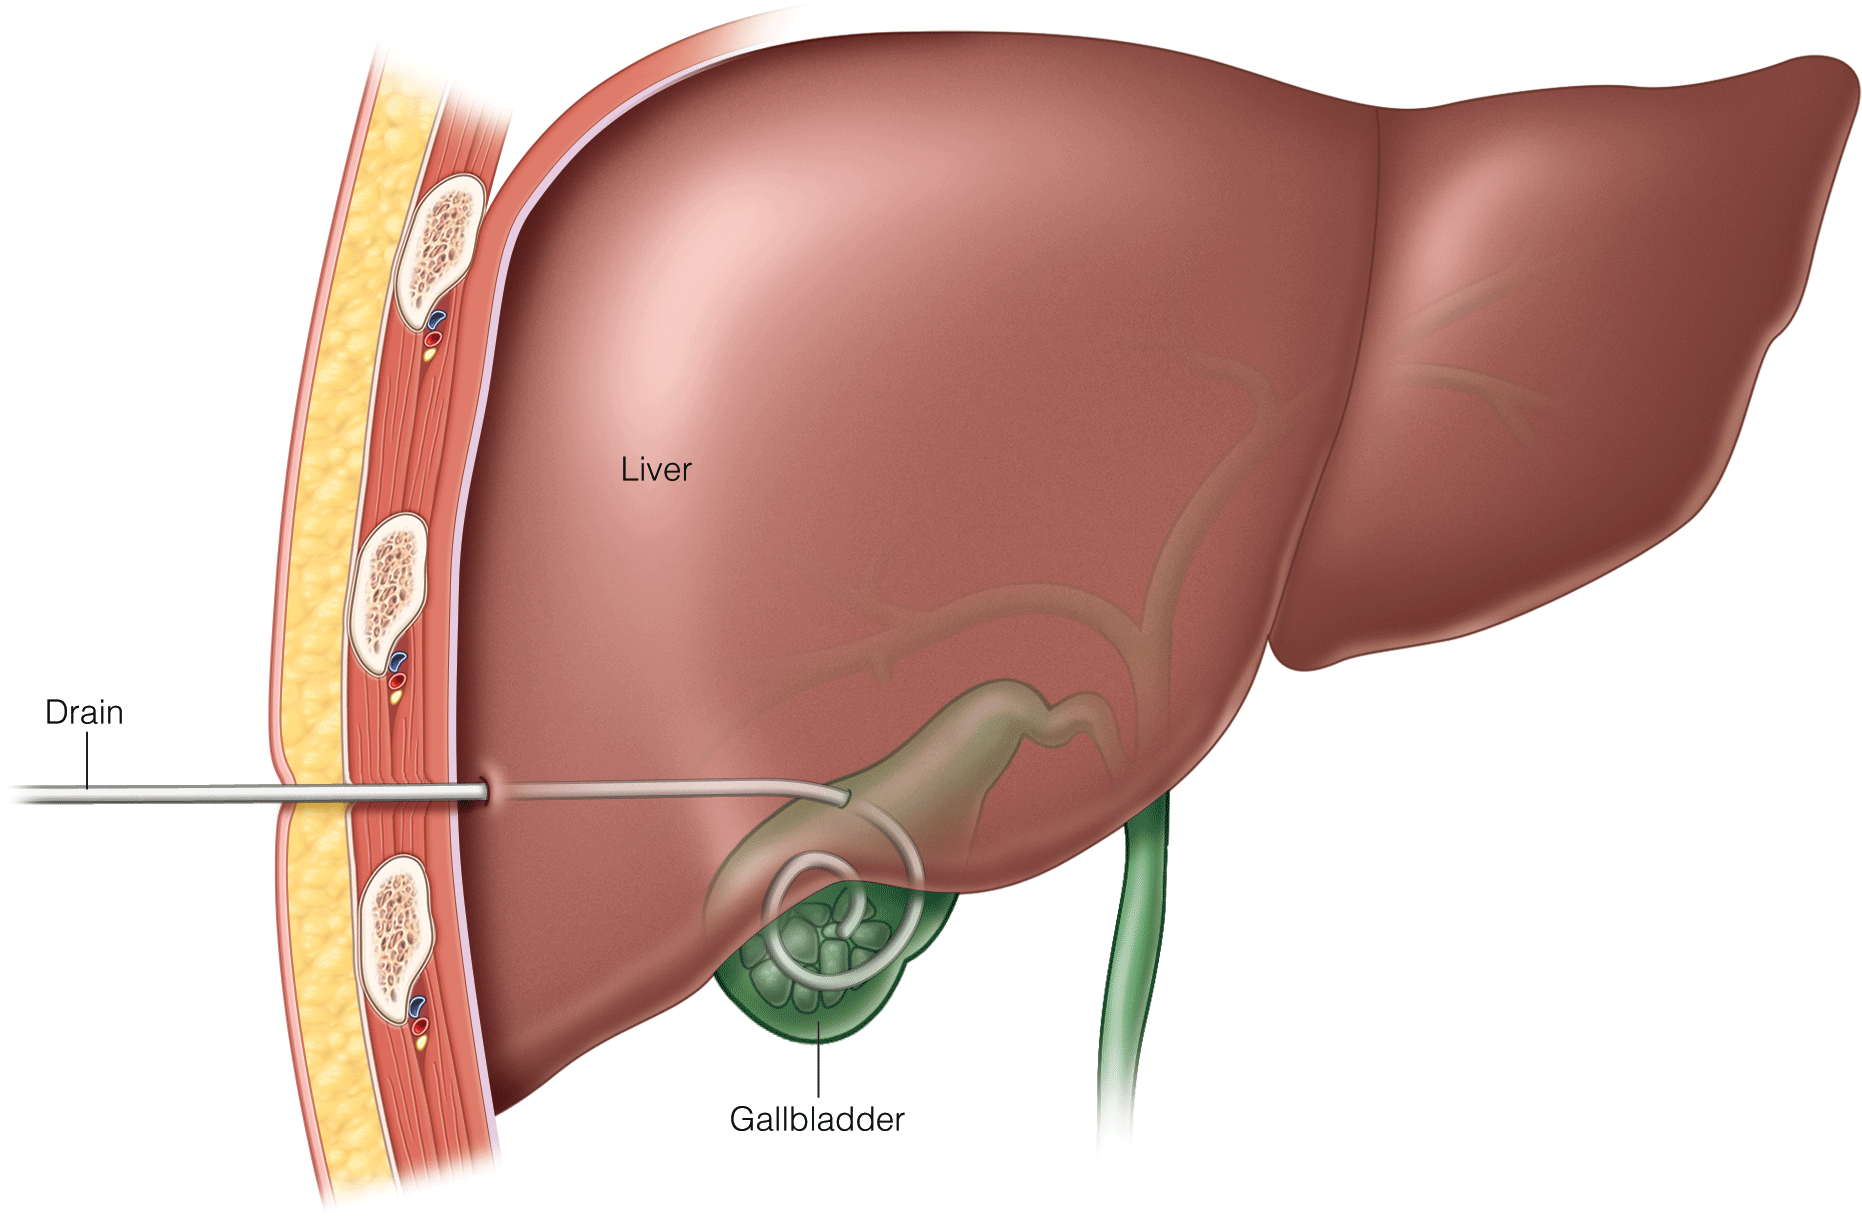

Acute appendicitis remains a therapeutic challenge during active pregnancy. Both laparascopic and open approaches can be considered; the techniques remain largely the same, with a few caveats. Fetal monitoring may be performed using a transvaginal or left lateral abdominal wall approach. For open appendectomy, ultrasonography and magnetic resonance imaging may provide direction for the incision. Laparascopic appendectomies should be approached with a open trocar placement in the midline, with direct visualization. Late-term pregnancies may require alternative approaches in the subcostal region, and the patient may be rolled with their left side down to facilitate exposure of the appendix and relieve pressure on the inferior vena cava.